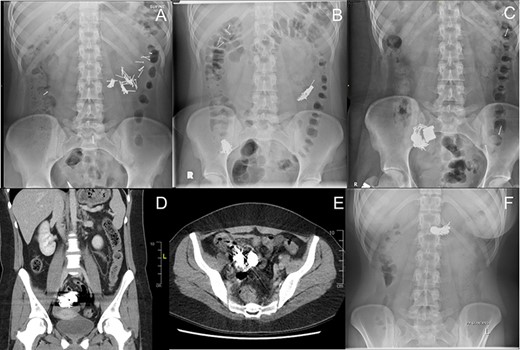

A 20-year-old female with a long history of complex borderline personality disorder, post-traumatic stress disorder and factitious disorder characterized by multiple admissions for overdoses and foreign body ingestions presented to the emergency room following ingestion of multiple 2-cm finishing nails, dispersed throughout the small bowel on abdominal X-ray (Fig. 1A). She was admitted for observation but on the fourth day left against medical advice (AMA) and returned after swallowing additional nails and one magnet. This magnet measured radiographically with a dimeter of 2 cm and height of 0.75 cm. She was taken for an esophagogastroduodenoscopy using a pediatric gastroscope but the magnet had already passed beyond the proximal jejunum (Fig. 1B). Three days later she left AMA for the second time and returned having overdosed on acetaminophen and swallowed additional magnets. Two days afterwards, following medical clearance by internal medicine, the X-ray in Fig. 1C was taken showing an additional four magnets aggregated with nails and the first magnet in the right lower quadrant. Serial X-rays demonstrated no movement of this complex. She remained stable with intermittent abdominal pain but no clinical or radiographical signs of bowel obstruction. Six days later, a computer tomography scan of the abdomen showed this complex to be lodged within the terminal ileum (Fig. 1D–E).

Radiographic series of sequentially ingested nails and magnets. The nails measured 2 cm long and magnets 2 cm in diameter and 0.75 cm in height. All dates are relative to initial ingestion of nails. (A) Day 1 – Nails in small bowel. (B) Day 6 – Additional ingestion of nails and a magnet. Original nails from A are clustered in right lower quadrant. (C) Day 9 – An additional four magnets have migrated to the right lower quadrant collection. (D) Day 15 – Coronal computer tomography (CT) view of nail-magnet collection in terminal ileum. (E) Day 15 – Axial CT view of nail-magnet collection in terminal ileum. (F) Day 26 – Smaller nail-magnet collection in transverse colon, 4 days after colonoscopic removal of the bulk of the collection.

After another 8 days without movement the patient was prepared for a colonoscopy. A large conglomerate of nails was extracted from the bowel wall of the ileocecal valve with endoscopic forceps and snare (Fig. 2A–C) and placed in the cecum (Fig. 2C). Some of these nails appeared to be extracted through the wall of the cecum, raising the possibly of an enteric-colonic fistula formed by impaction of the mass. Intubation of the terminal ileum did not show any retrievable objects. A Roth Net® retrieval basket was used to extract a total of 10 collected nails from the cecum (Fig. 2D). Subsequent X-rays over the next several days showed migration of the remaining objects in colon (Fig. 1F) which were subsequently eliminated.